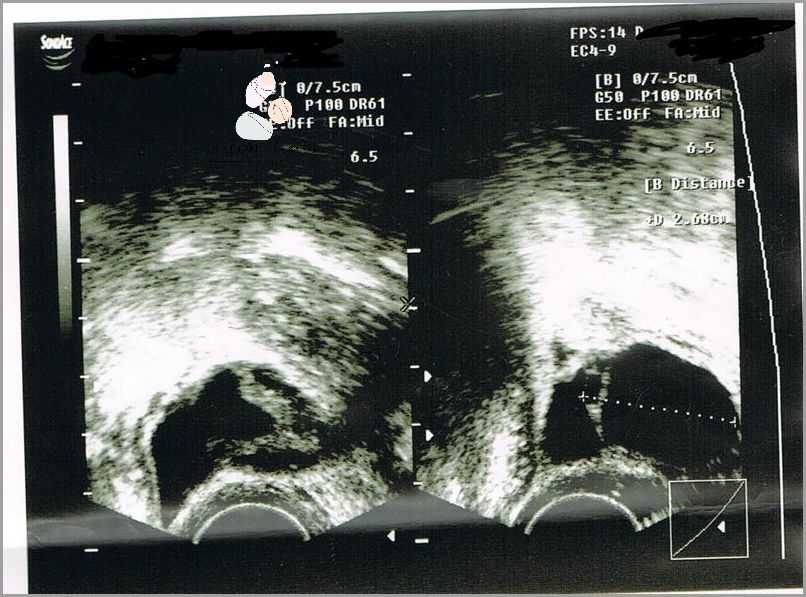

Torbiel na jajniku to nic innego jak pęcherzyk ciałka żółtego, który gromadzi się w jajniku. Pęcherzyk ten może mieć różne rozmiary i wypełnienie. Torbiele na jajnikach mogą występować u kobiet w każdym wieku, jednak najczęściej występują u kobiet w wieku 20-35 lat. Częstość występowania torbieli na jajnikach szacuje się na około 12%.

Torbiel na jajniku może być poważnym zagrożeniem dla zdrowia kobiety, szczególnie jeśli zostanie zdiagnozowana w trakcie ciąży. Choroba ta może powodować poważne komplikacje, takie jak poronienie lub przedwczesny poród. Dlatego ważne jest, aby kobiety, które mają torbiel na jajniku, poddawały się regularnym badaniom, aby upewnić się, że choroba nie postępuje, szczególnie jeśli chcą zajść w ciążę. W leczeniu torbieli na jajniku mogą być stosowane zarówno metody farmakologiczne, jak i chirurgiczne, w zależności od zaawansowania choroby. Lekarze często zalecają również monitorowanie poziomu hormonów, aby zapobiec powikłaniom.

Torbiel na jajniku to stosunkowo powszechne schorzenie, które może mieć poważny wpływ na ciążę. Jest to guz, który może rosnąć na jajniku z powodu zablokowania przepływu płynów w jajowodzie. W wyniku tego zatkania może dojść do stanu zapalnego, a nawet do wystąpienia torbieli.

Wpływ torbieli na ciążę może być zarówno korzystny, jak i niepożądany. Jeśli torbiel jest mała, prawdopodobnie nie będzie miała wpływu na ciążę. Jednak w przypadku większych torbieli może pojawić się wiele problemów, takich jak poronienia, przedwczesny poród lub niska masa urodzeniowa.

W przypadku ciąży związanej z torbielą na jajniku ważne jest, aby przestrzegać zaleceń lekarza i monitorować stan zdrowia. Może to obejmować regularne wizyty kontrolne, a także wykonywanie testów i badań, aby upewnić się, że torbiel nie ma wpływu na ciążę. W niektórych przypadkach lekarze mogą zalecić zabieg chirurgiczny, aby usunąć torbiel.

Podsumowując, torbiel na jajniku może wpływać na ciążę. W zależności od wielkości i lokalizacji torbieli skutki mogą być różne. Ważne jest, aby regularnie monitorować stan zdrowia i przestrzegać zaleceń lekarza, aby zminimalizować ryzyko niepożądanych skutków.